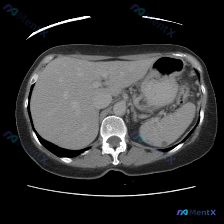

先看影像表现(单幅平扫CT)

- 肝脏:形态尚可,密度基本均匀,未见明显局灶性占位

- 脾脏:重点!脾脏大小形态正常,实质内靠近后缘可见一处圆形低密度小结节,边界尚清,密度接近水,无明显周围浸润或占位效应

- 其他:胃壁、脊柱、腹膜后未见明显异常,腹腔无积液,腹膜后脂肪间隙清晰